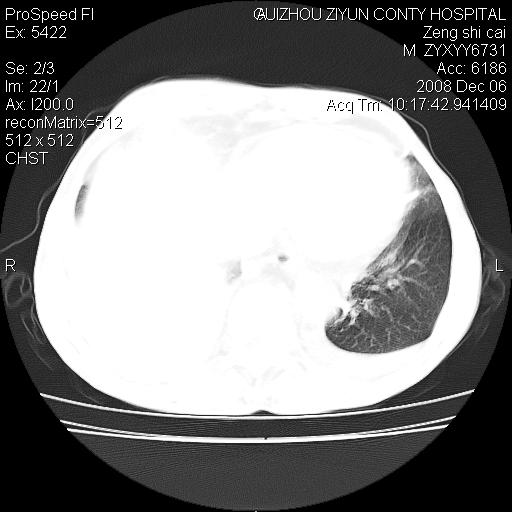

标题: CT16961:M、71岁,咳嗽半年,无血痰;胸片示右肺占位。 [打印本页]

标题: CT16961:M、71岁,咳嗽半年,无血痰;胸片示右肺占位。

右肺癌并纵隔淋巴结及胸膜转移可能性大

右肺癌并纵隔淋巴结及胸膜转移。建议气管镜

右肺纵隔型肺癌伴纵隔淋巴结及胸膜转移!

右肺纵隔型肺癌伴纵隔淋巴结转移!双侧胸水!

1)考虑右肺上叶纵隔型肺癌伴纵隔淋巴结转移。2)心包积液,双侧胸腔积液。

右肺癌并纵隔淋巴转移,腹膜后转移可能性大,两侧胸腔积液

右肺癌并纵隔淋巴结及胸膜心包转移,好多团团点点,看得有点想吐

右肺上叶纵隔型肺癌伴纵隔淋巴结转移。心包积液,双侧胸腔积液。

右上肺癌并纵隔淋巴结及胸膜转移。

右肺纵隔型肺癌伴纵隔淋巴结转移!双侧胸水\\心包积液

右肺纵隔型肺癌伴纵隔淋巴结及胸膜转移